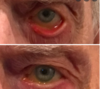

- Severely painful red eye

- Red eye

- Fixed dilated pupil

- Corneal haze

- Teary